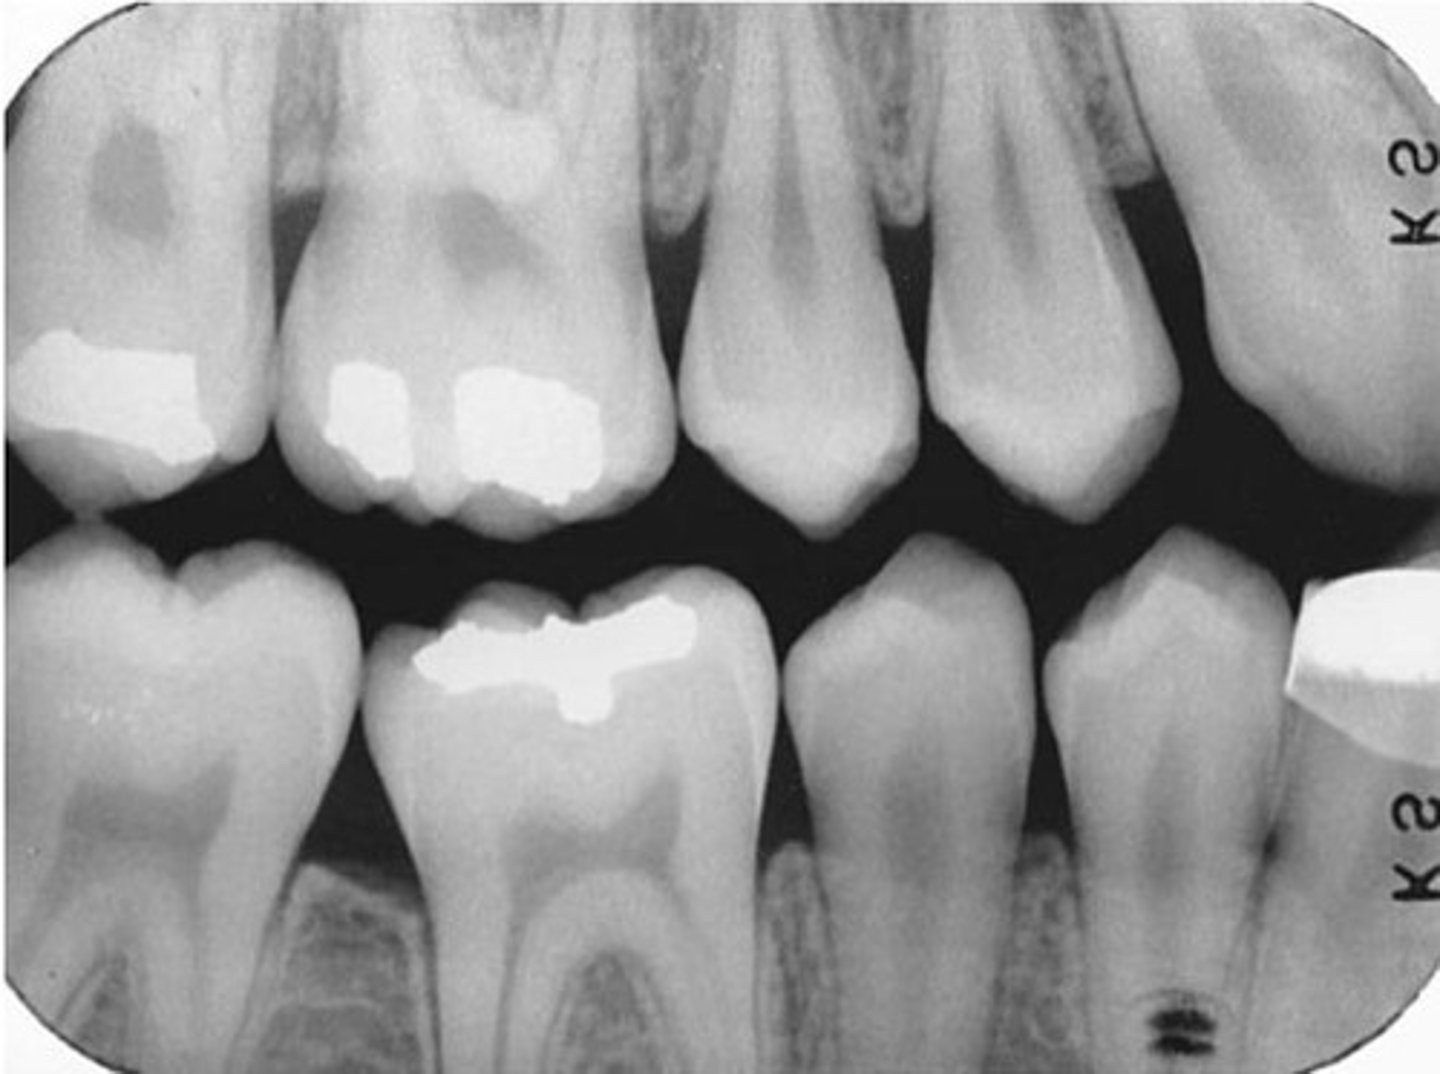

method used to examine the interproximal surfaces of teeth

-used to monitor the progression of dental caries, assess existing restorations, and examine the crestal bone levels between teeth

used to examine the crowns of both maxillary and mandibular teeth on a single image

appear as thin radiolucent lines between adjacent tooth surfaces

the area where the contact area of one tooth is superimposed over the contact area of an adjacent tooth.

Correct horizontal angulation:

-The central ray is directed perpendicular to the curvature of the arch and through the contact areas of the teeth.

incorrect horizontal angulation

results in overlapped contact areas